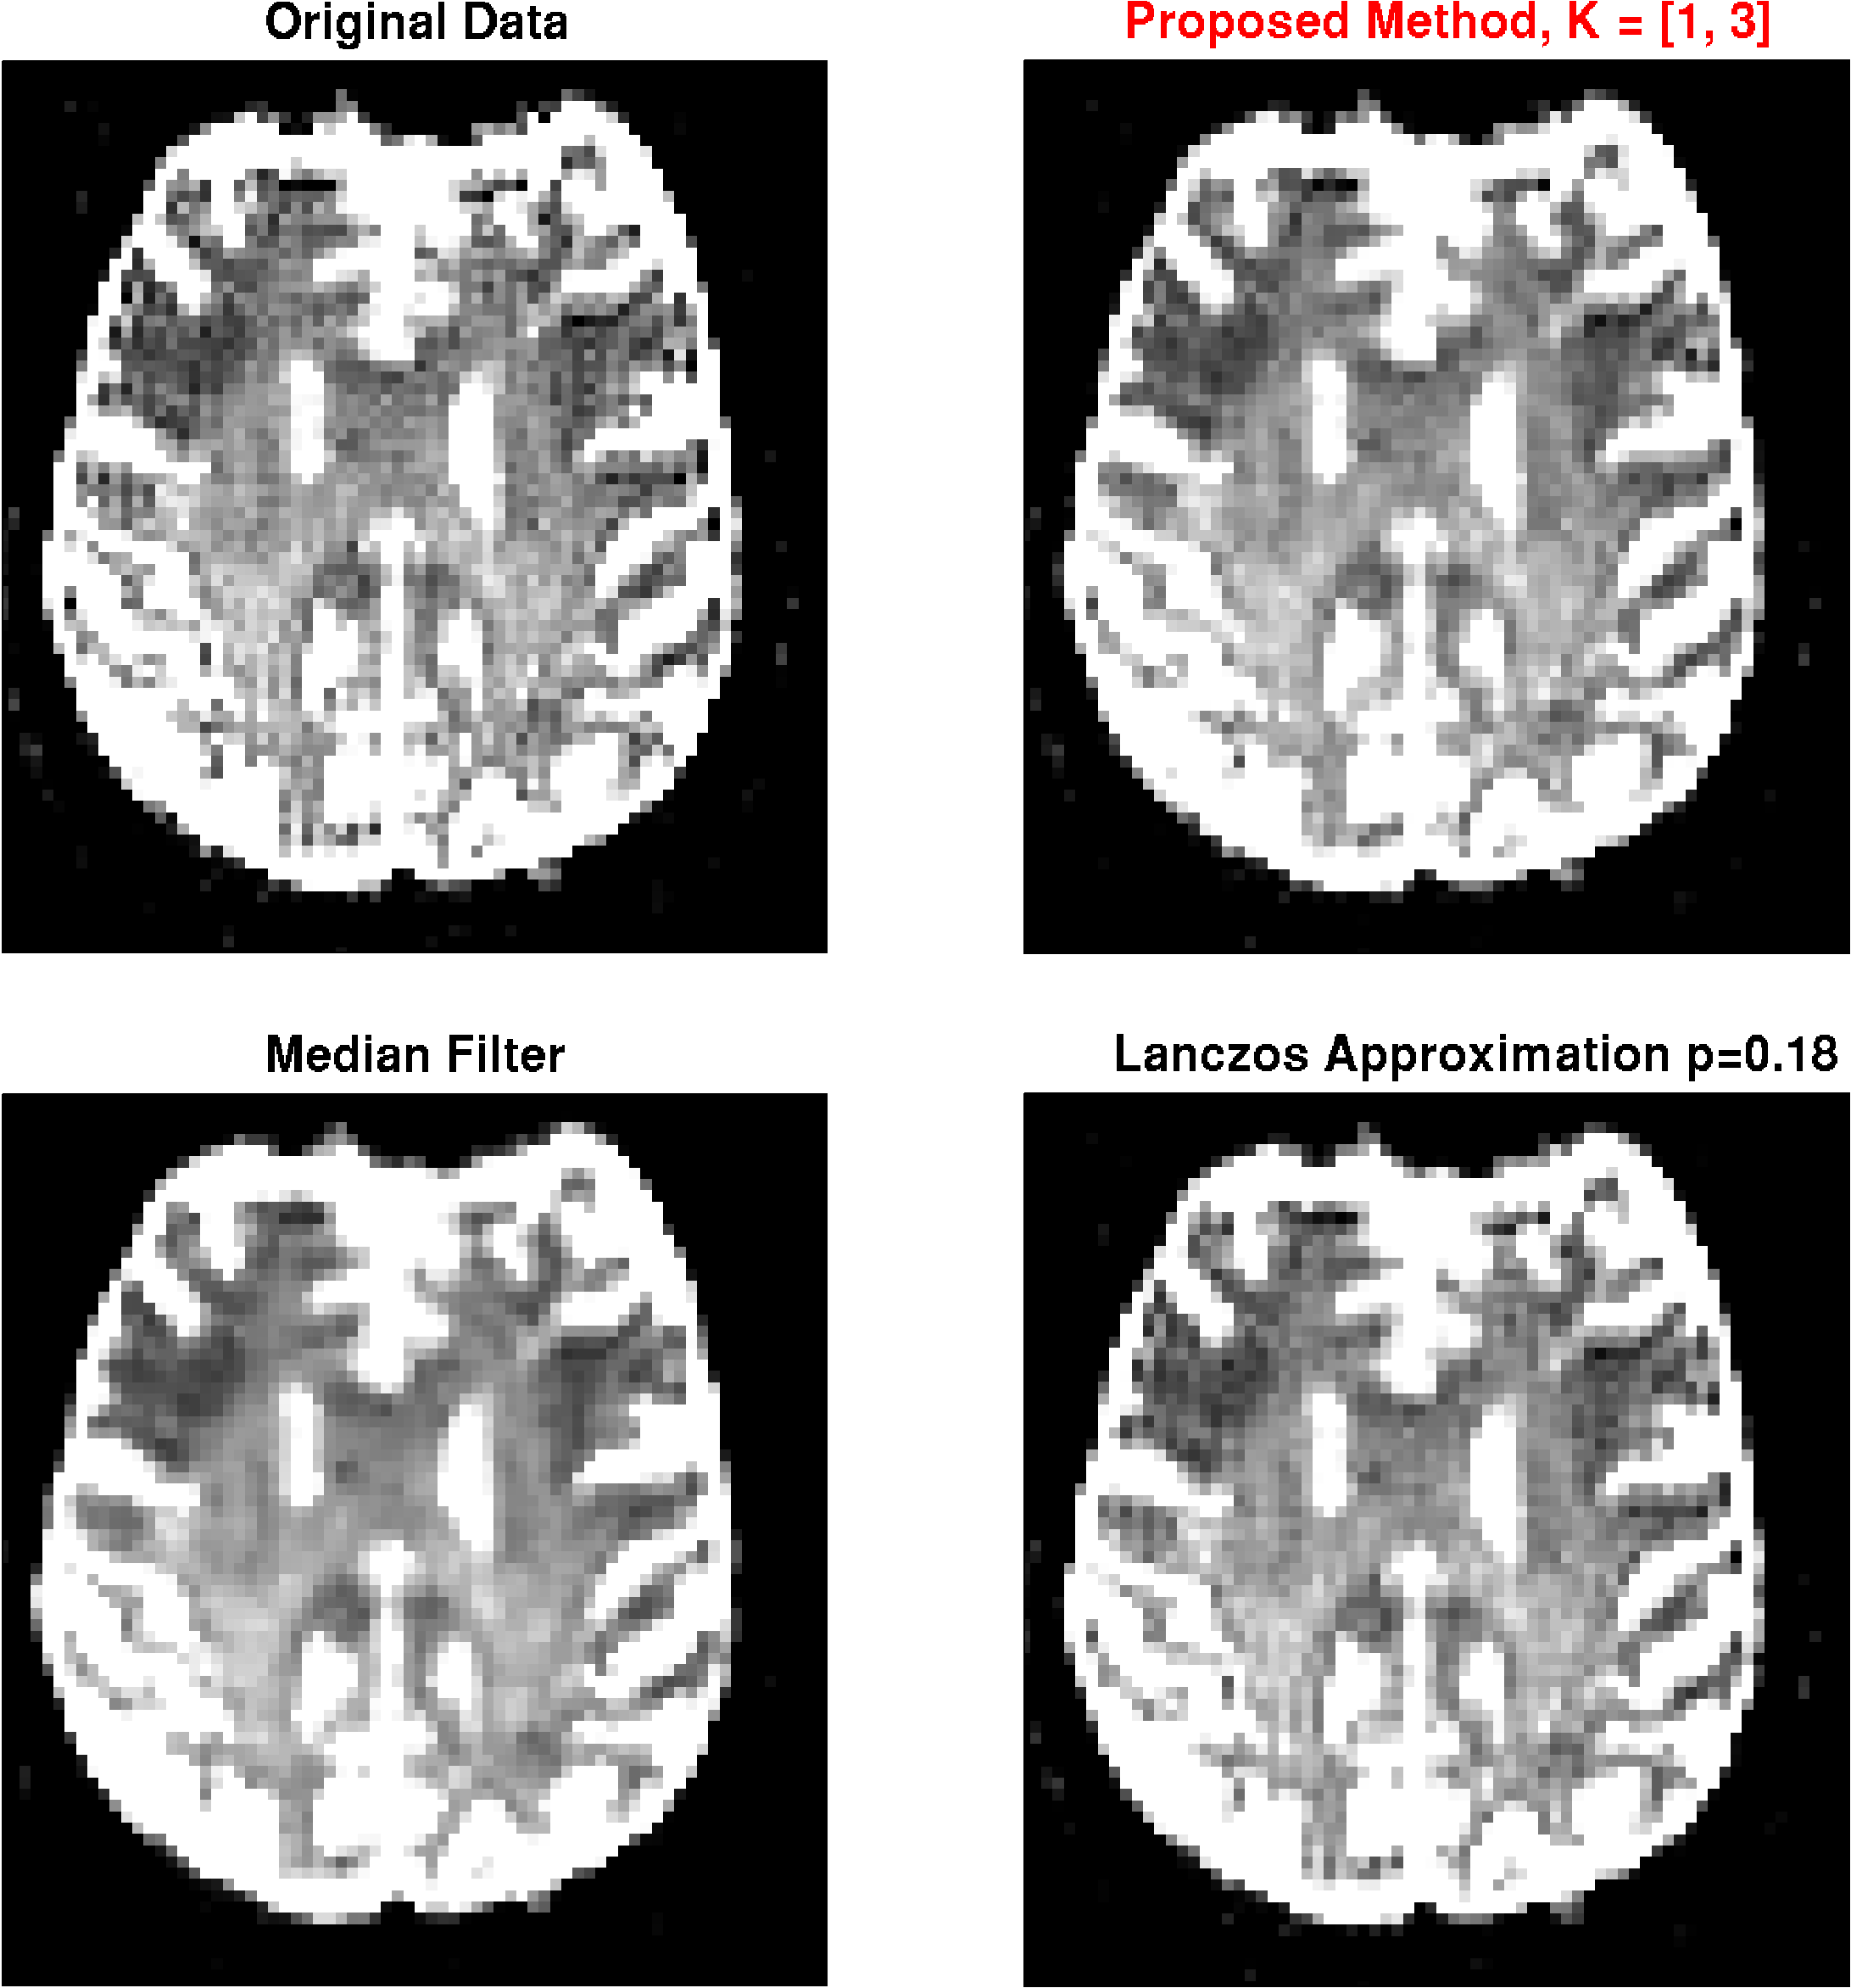

MRI images

The results for DWI measurements are shown for one slice in Fig. 6. Apparently, the -images exhibit strong ringing artifacts, which is even more emphasized after diffusion calculation. The artifact can be reduced with both, the median filter and the Lanczos approximation with , however, at the cost of strong smoothing. With the proposed method on the other hand, the artifact can virtually completely be removed with minimal filtering. Results from the -weighted image given in Fig. 7. The findings are basically the same as for the DWI measurement.